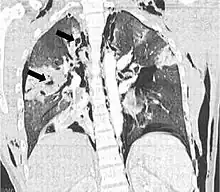

| Coronal CT scan showing lucencies (pale areas in radiography) in the lung caused by pulmonary lacerations on the left of the image (black arrows) | |

Pulmonary laceration may not be visible using chest X-ray because an associated pulmonary contusion or hemorrhage may mask it.[1][9] As the lung contusion clears (usually within two to four days), lacerations begin to become visible on chest X-ray.[3] CT scanning is more sensitive and better at detecting pulmonary laceration than X-rays are,[1][5][12][15] and often reveals multiple lacerations in cases where chest X-ray showed only a contusion.[12] Before CT scanning was widely available, pulmonary laceration was considered unusual because it was not common to find with X-ray alone.[12] On a CT scan, pulmonary lacerations show up in a contused area of the lung,[9] typically appearing as cavities filled with air or fluid[16] that usually have a round or ovoid shape due to the lung's elasticity.[4]

Hematomas appear on chest radiographs as smooth masses that are round or ovoid in shape.[1] Like lacerations, hematomas may initially be hidden on X-ray by lung contusions, but they become more apparent as the contusion begins to heal.[1] Pneumatoceles have a similar shape to that of hematomas but have thin, smooth walls.[17] Lacerations may be filled completely with blood, completely with air, or partially with both.[4] Lacerations filled with both blood and air display a distinctive air-fluid level.[4] A single laceration may occur by itself, or many may be present, creating an appearance like Swiss cheese in the radiography of the lung.[4]